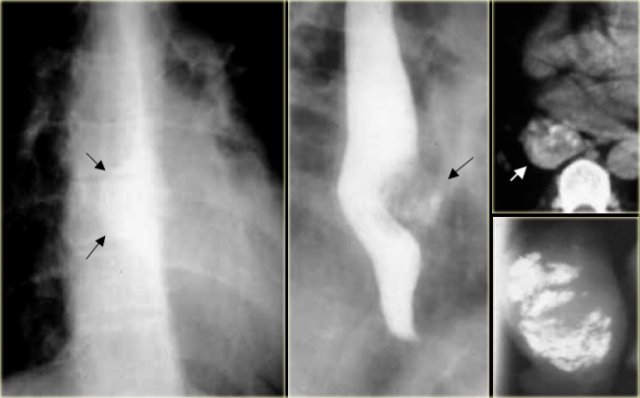

On the left a patient with an esophagus hematoma.

He presented with chest pain and dysphagia after vomiting.

Aside from tortuous aorta chest radiograph is normal.

The barium study shows a narrowed lumen (arrows) on AP view and flattened lumen on lateral view (arrowheads) suggestive of a intramural hematoma.

On CT the diagnosis of an intramural hematoma was confirmed.

A high density mural hematoma (arrowhead) is seen next to NG tube (arrow).

Following conservative treatment, six months later the barium study was normal.

On the left a patient who had a complicated endoscopy.

Instrumentation caused a mucosal tear and dissecting intramural hematoma resulting in double lumen with separating stripe of mucosa (arrows).